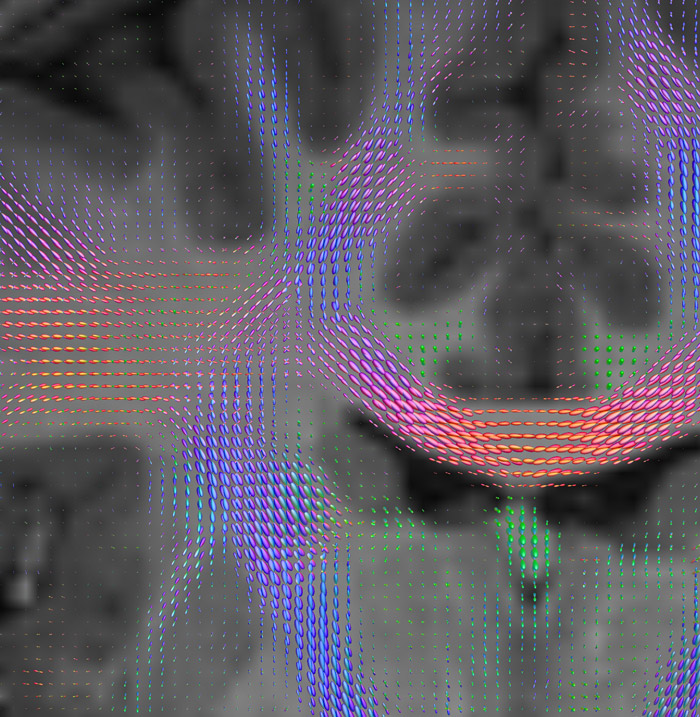

CSD of multishell DWI results in the white matter FOD at each voxel. Unlike the conventional diffusion tensor model, this approach enables accurate modeling of multiple fiber populations within a single voxel.

Crossings of the corpus callosum, corticospinal tracts, and the superior longitudinal fasciculus are shown.